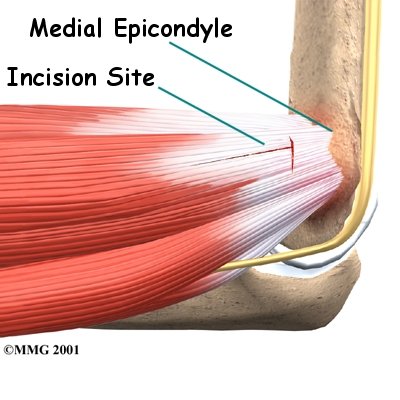

A commonly used surgery for golfer's elbow is called a medial epicondyle release. This surgery takes tension off the flexor tendon. The surgeon begins by making an incision along the arm over the medial epicondyle. Soft tissues are gently moved aside so the surgeon can see the point where the flexor tendon attaches to the medial epicondyle.

The flexor tendon is then cut where it connects to the medial epicondyle. The surgeon splits the tendon and takes out any extra scar tissue. Any bone spurs found on the medial epicondyle are removed. (Bone spurs are pointed bumps that can grow on the surface of the bones.) Some surgeons suture the loose end of the tendon to the nearby fascia tissue. (Fascia tissue covers the muscles and organs throughout your body.)

Your surgeon will look at the ulnar nerve, to make sure that it is not being pinched. If the nerve looks fine, the skin is then stitched together.